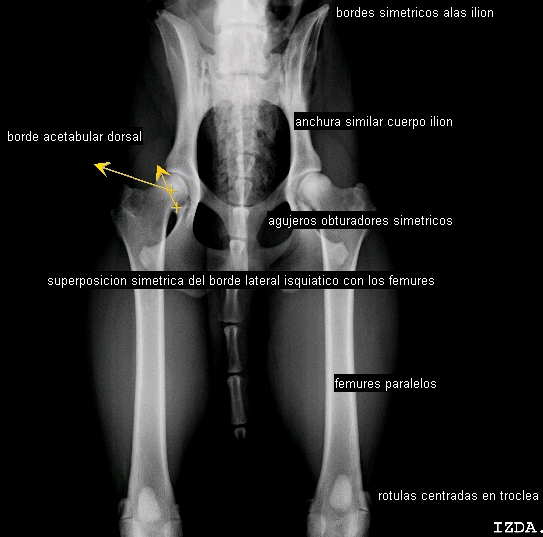

Displasia de Cadera

Es la enfermedad de carácter hereditario más conocida por propietarios, criadores, y veterinarios, afectando a un gran número de razas de tamaño medio y grande fundamentalmente. Los animales afectados presentan un desarrollo anómalo de la articulación coxofemoral, con una inadecuada coaptación entre la cabeza del fémur y el acetábulo, causando un desgaste prematuro de los cartílagos articulares, este defecto en la conformación desencadena unos cambios de tipo artrítico causantes del cuadro sintomático de la enfermedad.

La etiología de la enfermedad es poligénica multifactorial, hay varios genes que van a determinar la estructura de la cadera (genotipo), pero estos genes se expresarán en mayor o menor medida según sea la influencia del medio ambiente (alimentación, ejercicio, hábitat, etc.), de la interacción de estos dos factores (genotipo y medio ambiente), obtendremos como resultado un tipo concreto de cadera (fenotipo).